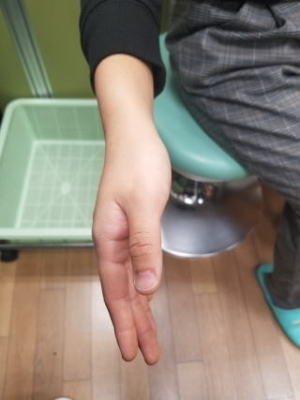

朝起きたら手が動かないと来院されました。典型的な橈骨神経麻痺です。ご厚意により写真掲載を許可して頂きました。ありがとうございます。

運動麻痺:前腕回外、手関節伸展、MP関節伸展(手関節背屈位)

母指-示指指間部の知覚障害